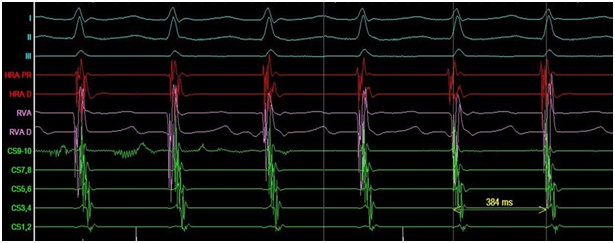

The ECG documented narrow complex short RP tachycardia with ventricular response of 140bpm. The patient noticed that around the time that the symptoms of palpitations appeared for the first time, she had lost the sense of smell and started to suffer from urinary incontinence but didn’t search for medical advice. She was assessed in our clinic and decision was made to proceed with electrophysiology study. The study showed dual atrio-ventricular (AV) node physiology. Supra-ventricular tachycardia (SVT) (Figure 1) was induced at a cycle length (CL) of 380ms with ventriculo-atrial interval of 35ms, and entrainment maneuvers supported typical AV node re-entry tachycardia as the working diagnosis. Slow pathway ablation was performed with successful outcome. During isuprel administration and atrial pacing incessant atrial tachycardia (AT) with two different CL of 360 and 320ms was provoked (Figure 2).

Figure 2 Incessant atrial tachycardia.

Electrophysiological study: I, II, III- ECG leads; RVA- Right ventricular apex; CS- coronary sinus; P- proximal electrodes; D- distal electrodes; Map- mapping catheter.